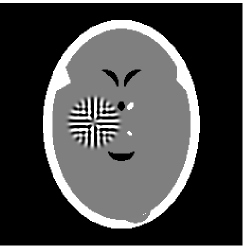

Furthermore, we used the classic ART iteration as the iteration operator in our numerical experiments. In order to compare the proposed superiorization algorithm with the classic superiorization algorithm, we applied the classic superiorization and -PP superiorization algorithm to two phantoms (see figure 1). The first one is the Shepp-Logan phantom[30], and the second one is the head phantom with a ghost which is invisible at 22 specified projection directions [10, 31]. In addition, we compare the performances of the two algorithms for the noiseless and noised data with different projections. In all experiments, the noised projection data was corrupted by additive Gaussian white noise with variance . We record the iterations, running time of program and mean square error (MSE) of different algorithms, where MSE is computed by

3.2 Ghost phantom

Noiseless projection data: Since the ghost in this phantom is invisible at 22 directions [10, 11], the reconstruction images usually suffer from artifacts. in our simulations, the projection data were collected in 112 and 82 directions: 90 and 60 with equal angle increments from to and 22 specified views in which the ghost is invisible [10]. Iteration procedures were terminated when for the noiseless projections.

The reconstruction images from the noiseless projection data were shown in the Fig. 6. For comparison, Table 3 present the iterations, MSE, Res and running time(RT) of different reconstruction results.